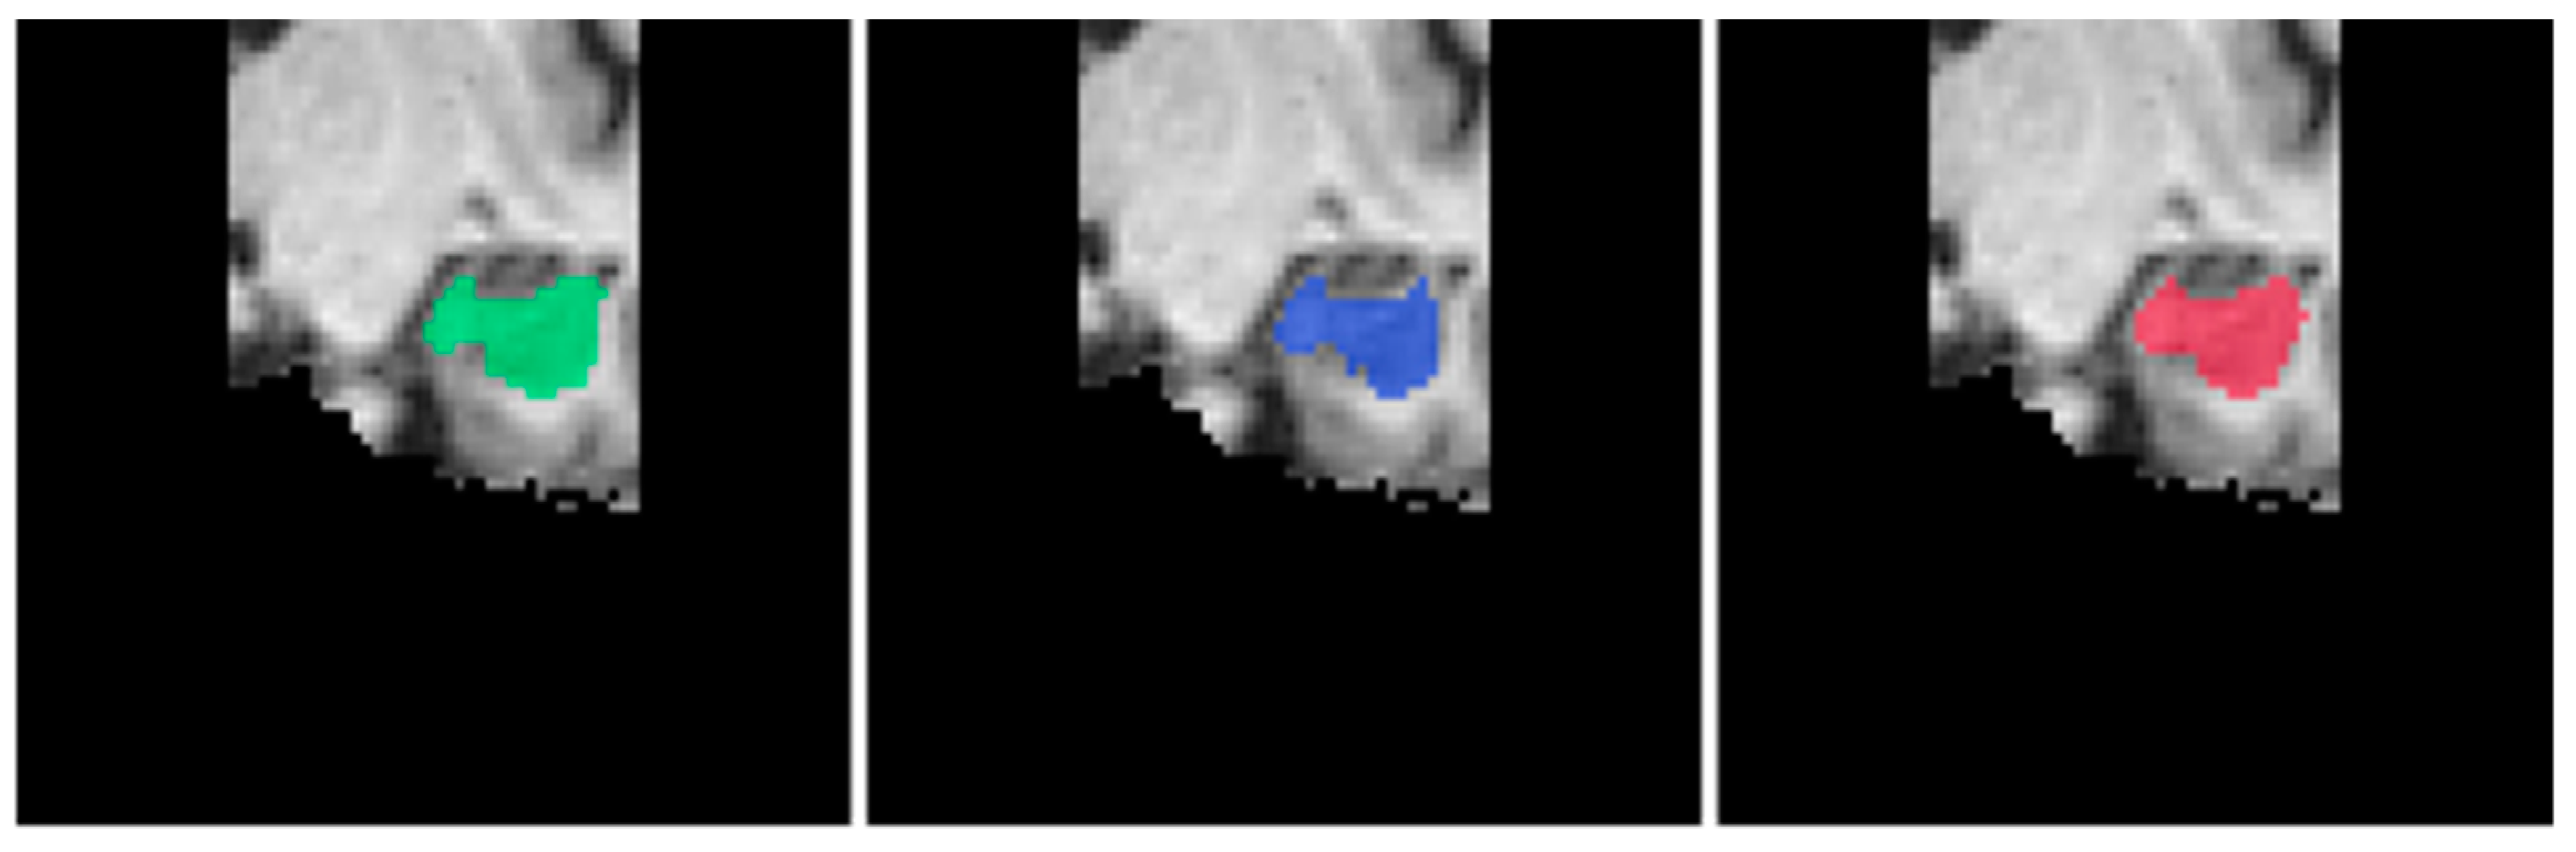

For the segmentation of the left hippocampus, we can see in Table 8 that EnsembleUSegNetL obtained higher DSC, precision, and recall scores as compared to 3D U-NetL. In terms of the hippocampus segmentation task, the higher precision and recall indicated that when compared to 3D U-NetL, EnsembleUSegNetL was less likely to falsely identify non-hippocampus voxels as part of the hippocampus and also was more capable of correctly detecting the actual hippocampus voxels. This meant that the EnsembleUSegNetL outperformed the 3D U-NetL when it came to hippocampus segmentation, which was reflected in the higher DSC score. An extracted coronal slice from the predicted segmentation masks and the ground truth hippocampus mask is shown in Figure 15 below.

Figure 15.

Sample coronal slices of predicted left hippocampus segmentation masks overlaid on the brain MRI in the order of ground truth (green), EnsembleUSegNetL (blue), and 3D U-NetL (red) from left to right.

For the segmentation of the right hippocampus, it was observed that in comparison to 3D U-NetR, while EnsembleUSegNetR had higher DSC and precision scores, it performed considerably worse in terms of recall (0.86122 for 3D U-NetR vs. 0.83913 for EnsembleUSegNetR). The worse recall score meant that the EnsembleUSegNetR was less likely to correctly identify all the voxels belonging to the hippocampus. Conversely, it was also noted that EnsembleUSegNetR performed much better in terms of precision as compared to 3D U-NetR (0.90486 vs. 0.87576). This indicated that the EnsembleUSegNetR was much less likely to erroneously predict non-hippocampus voxels to be part of the hippocampus. Together, these observations suggested that the EnsembleUSegNetR had more conservative predictions for the right hippocampus as compared to 3D U-NetR. This can be seen in Figure 16 below, where the yellow circles highlight the region that EnsembleUSegNetR failed to detect as part of the right hippocampus.

Figure 16.

Sample coronal slices of predicted right hippocampus segmentation masks overlaid on the brain MRI in the order of ground truth (green), EnsembleUSegNetR (blue), and 3D U-NetR (red) from left to right. Yellow circles show the hippocampus region missed by EnsembleUSegNetR.